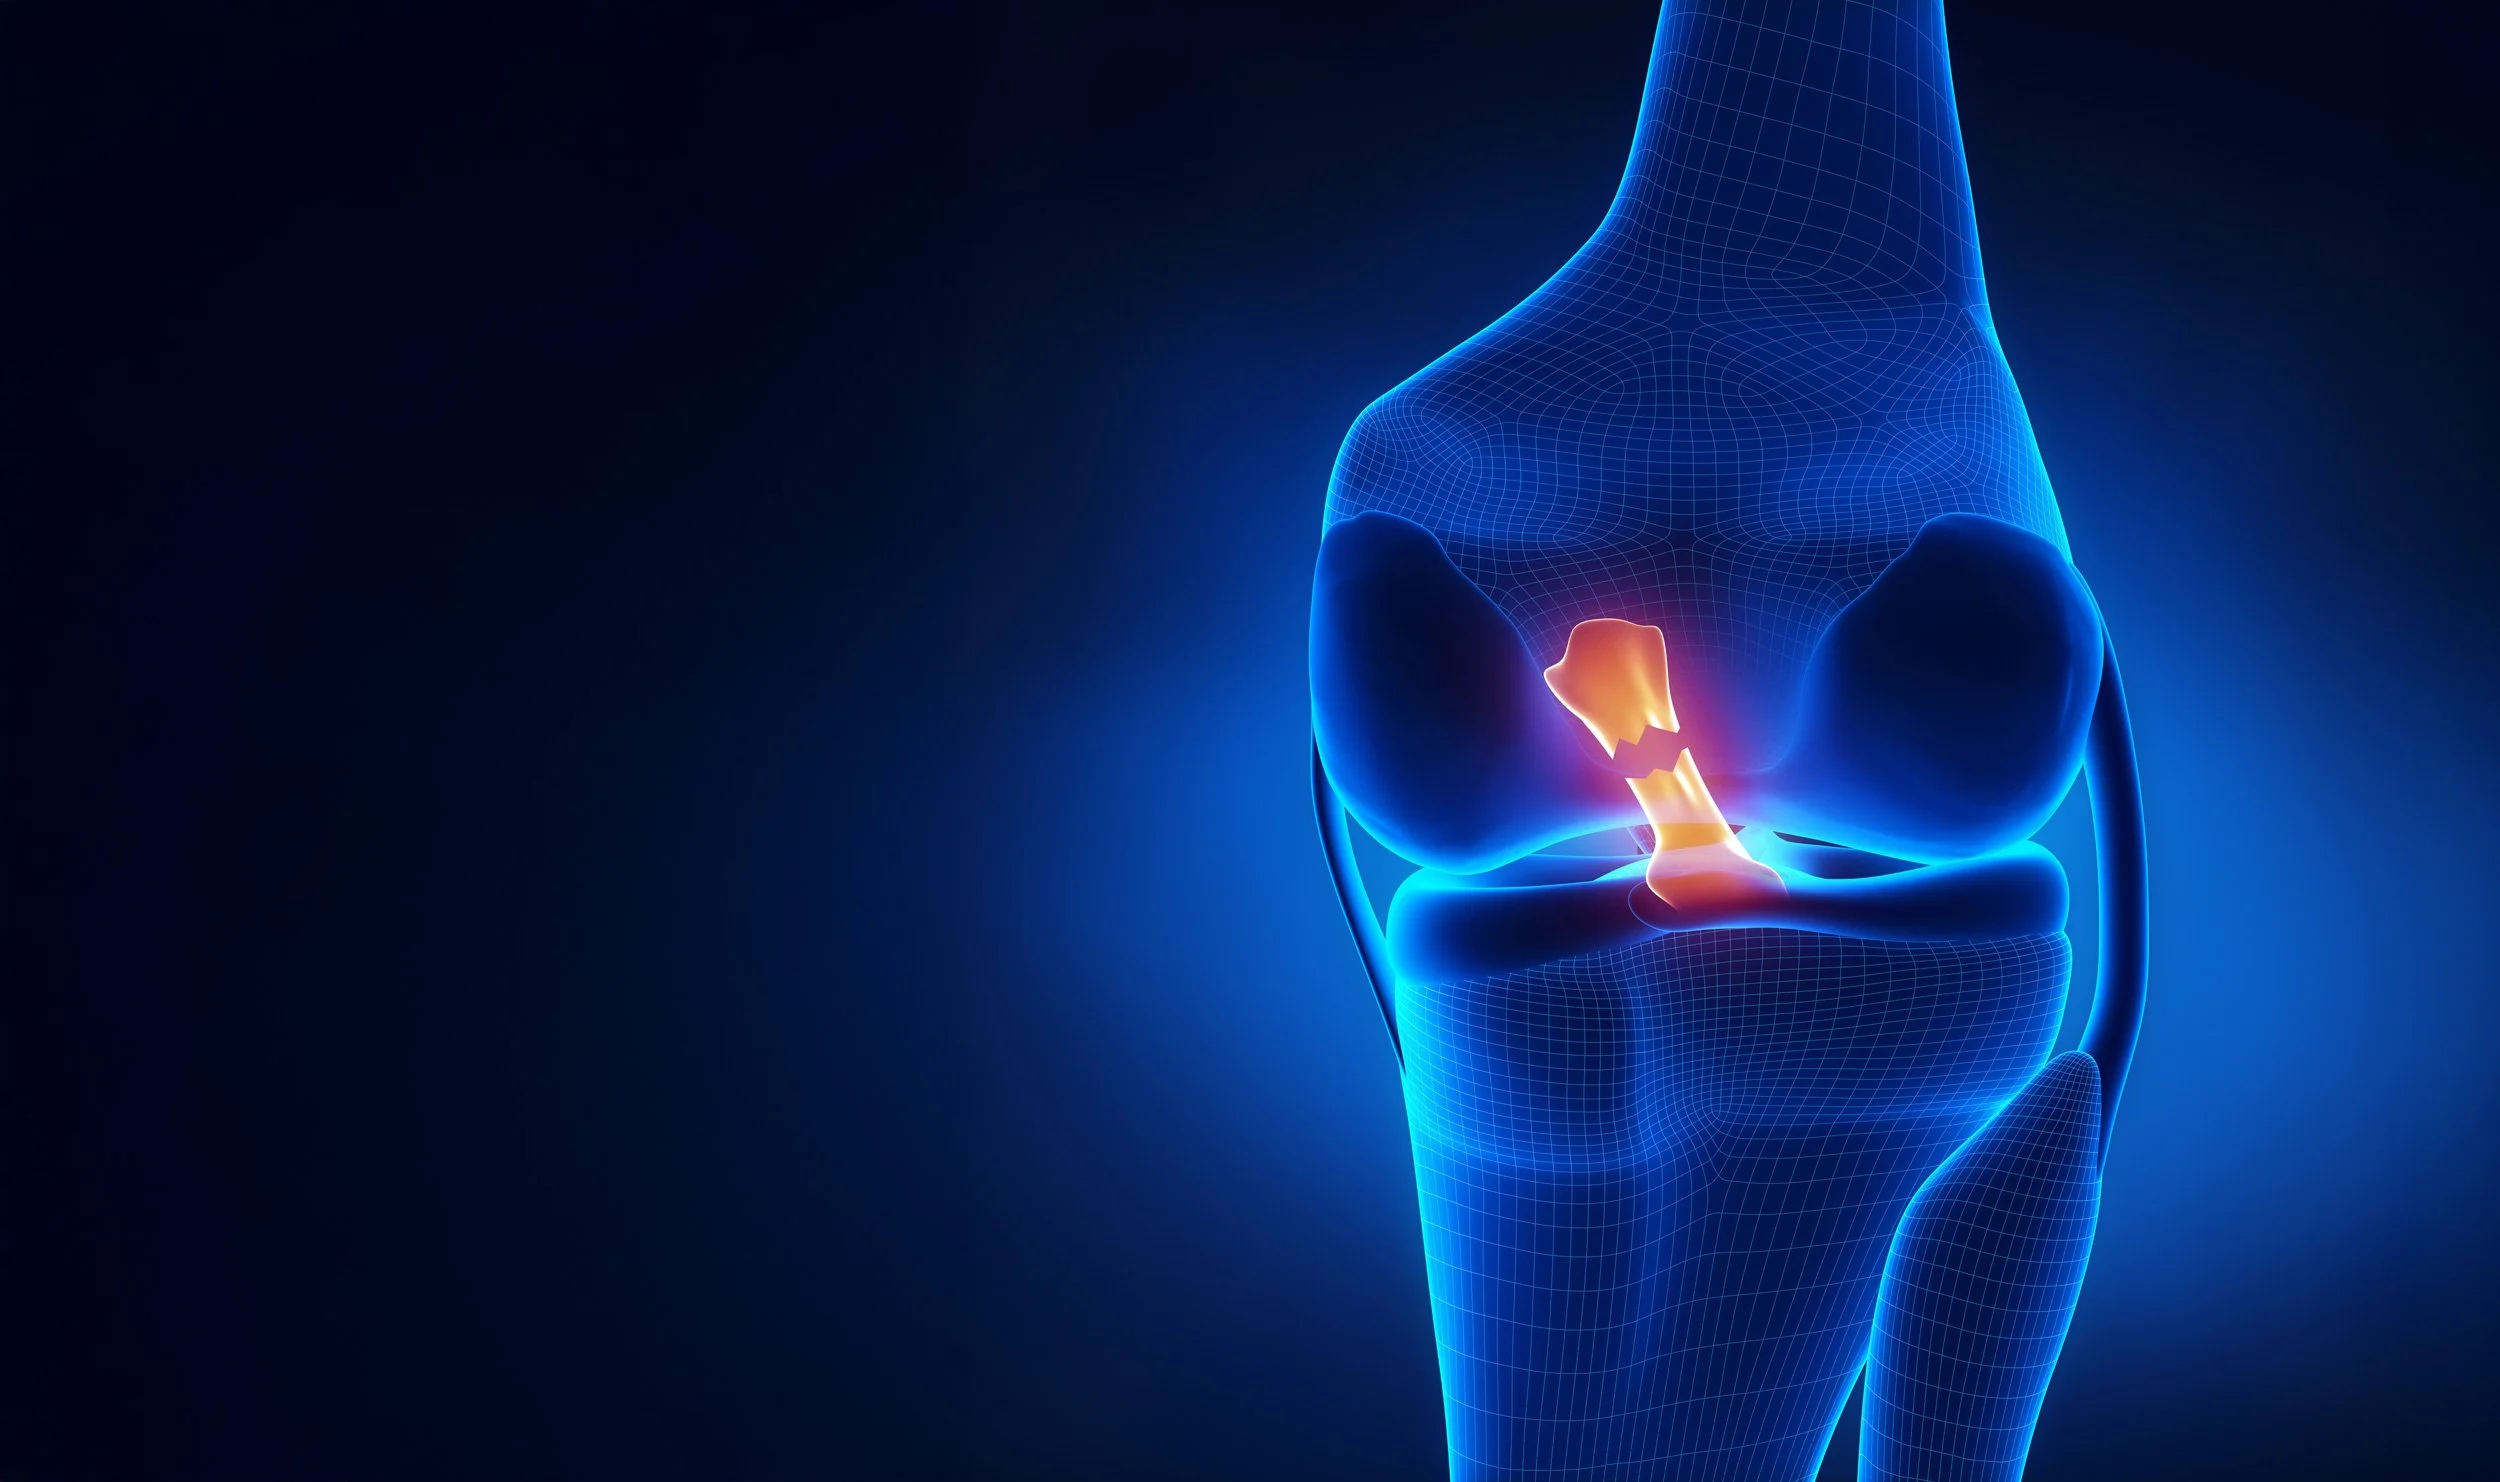

Bone Ligament Tendon

Revolutionizing Soft-Tissue Surgery with

Next-Generation Biomaterials

At BLT, we are driving innovation in orthopaedic soft-tissue surgery through evidence-based biomaterial science.

Our proprietary decellularization technology is developed to produce biocompatible scaffolds intended for the reinforcement and restoration of dense connective tissue. Engineered with integration and long-term performance in mind, these implants are designed to support the healing process and intended to serve as an alternative to autografts, thereby eliminating the need for graft harvesting and reducing associated donor site morbidity and additional surgical wound sites.